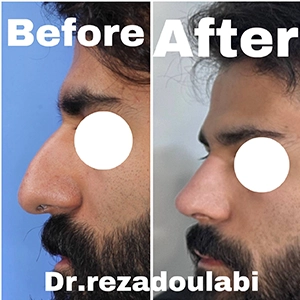

تمرکز بر نتایج «طبیعی و متناسب با صورت» بهجای تغییرات افراطی.

رفع قوز استخوانی و اصلاح زاویه بینی و پیشانی

🎯 انتخاب بهترین جراح بینی در تهران

اگر به دنبال بهترین جراح بینی در تهران هستید، تجربه، نمونه کارهای موفق، ارتباط حرفهای با بیمار و آشنایی با تکنیکهای مدرن جراحی، معیارهایی مهم برای انتخاب شما هستند. حتماً عکسهای قبل و بعد عمل بینی بیماران را ببینید و در جلسه مشاوره تمام انتظارات خود را مطرح کنید.

👨⚕️ درباره دکتر سید رضا سید محمد دولابی

دکتر سید رضا سید محمد دولابی، جراح و فوقتخصص گوش، حلق، بینی و جراحی سر و گردن، از برترین پزشکان کشور در زمینه جراحی زیبایی و درمانی بینی و سینوس بهشمار میرود. ایشان فلوشیپ فوق تخصصی خود را در تهران و فرانکفورت با بالاترین رتبه علمی دریافت کرده و موفق به گذراندن امتحان بینالمللی USMLE نیز شدهاند.